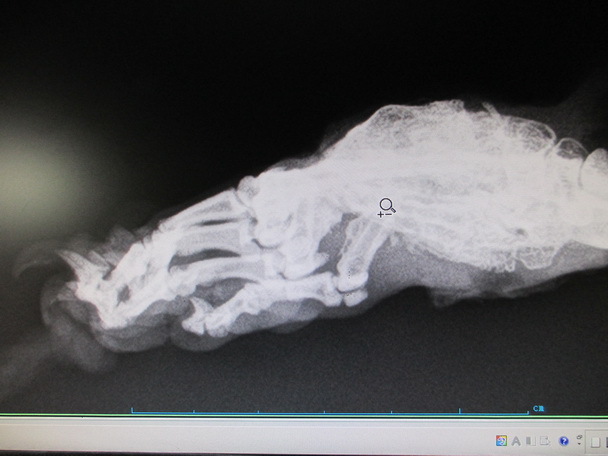

主題: 疑似車禍受傷又被大狗追咬的傷貓 申請者姓名: 詹惠文 花色: 申請日期: 2012-10-23 15:07:39 申請者部落格: 申請者臉書網址: 所在縣市/合作醫院: 台北市/欣旺動物醫院 治療費用: 20000元 需求人數: 22人 已結案 (2013-06-27 13:51:54) 報名人員: 收夕(已付款)、泰迪貓(已付款)、Arthur Jo(已付款)、chiawei(已付款)、Lulu Hsieh(已付款)、林宜屏(已付款)、Joyce(已付款)、林苡瀅(已付款)、鍾慶燁(已付款)、Yen Tzu(已付款)、Karen Chang、J2(已付款)、William Chang(已付款)、潘逸群(已付款)、潘逸群(已付款)、夏實舞(已付款)、周星星(已付款)、Shu-Ting Chuang(已付款)、Roxy Chen(已付款)、陳小茜(已付款)、S.Wish Kong(已付款)、春卷(已付款)、王千枝(已付款)、 候補人員: 動物病情說明: 黑白公貓為中山區行政里行天宮後面一位70歲愛媽呂媽媽餵養區的貓.呂媽媽表示有多週不見該貓出來覓食.之後有一鄰居通報見該貓腳受傷又被一隻大狗追咬.愛媽經多日誘捕終於抓到傷貓於7/19送醫.醫生表示.該貓腳傷潰爛嚴重.骨頭有外露.可能需要截肢.但呂媽媽表示.該貓是在外流浪.如果截肢恐生存不易.希望能保留左後肢.所以採取皮膚縫合+藻酸鈣敷料惟須費時多日.經過3個月的辛苦治療終於復原.目前由呂媽媽帶回.視狀況R回原地.此筆醫藥費懇請大家的幫忙.感恩